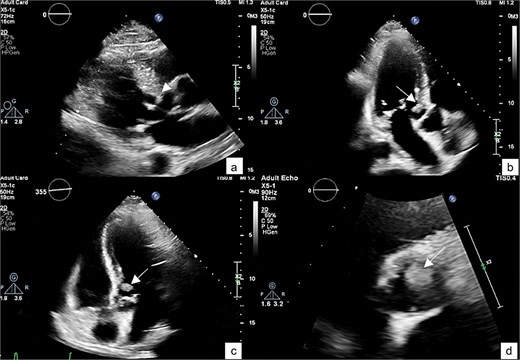

He was referred to our hospital for further evaluation by the cardiology and cardiothoracic surgery departments. On admission, he was afebrile with a heart rate of 62 beats per minute, blood pressure of 148/73 mmHg, and respiratory rate of 20 breaths per minute. No abnormalities were noted in any other system. Laboratory findings were unremarkable. An ECG demonstrated normal sinus rhythm. TTE re-evaluation revealed a normal LVEF of 72% with a 1.2 × 1 cm hypermobile cardiac mass attached to the basal anteroseptal wall near the LVOT without evidence of LVOT obstruction; there were no valvular lesions or thrombus seen (Figs 1 and 2). Coronary angiography showed normal coronary vessels. Due to its nature and clinical presentation, the patient was set for early surgical excision of the mass 3 days after admission.

A TTE showing a small-rounded mass attached to the LV septum (arrow), which can be seen protruding into the LVOT in various echocardiographic views: Parasternal view (a), parasternal long axis view (b), 5-chamber view (c), and short-axis view of aortic valve (d).